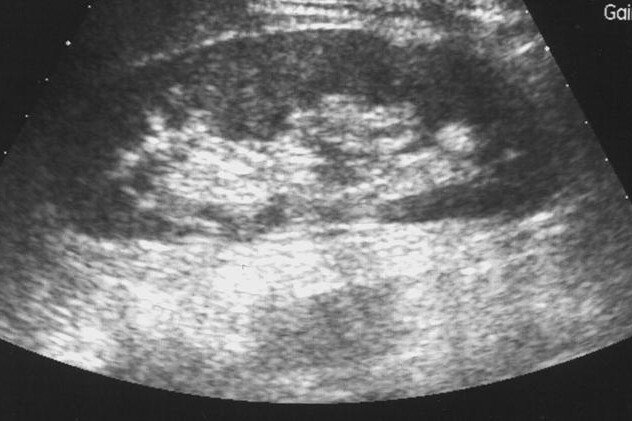

Ledvinové kameny opouštějí tělo močí, pokud jsou malé, může to proběhnout bez příznaků. Pokud jsou kameny větší než 2–3 mm mohou způsobit ucpání močovodu a způsobit překážku odtoku moči. Ve snaze o překonání této překážky se svalovina ve stěně močovodu začne křečovitě stahovat a uvolňovat. To je příčinou vzniku urputných bolestí, které jsou nazývané jako ledvinová kolika. Bolest při ledvinových kamenech má charakteristický kolísavý charakter. Bolest je pociťována v bederní oblasti a vystřeluje podél močovodu do podbřišku, šourku či stydkých pysků. Časté jsou doprovodné příznaky jako nevolnost a zvracení, může dokonce dojít k zástavě pohybu střev. Další příznaky ledvinových kamenů je přítomnost krve v moči. Důvodem je drobné poranění vnitřní stěny pánvičky, močovodu či stěny močového měchýře při pohybu kamene. Setkáváme se s méně častým močením, bolestivým močením a přítomností hnisu v moči. Závažnou komplikací je rozvoj hydronefrózy. Hydronefróza je patologicky vzniklé rozšíření ledvinné pánvičky (připojuje ledvinu k močovodu) hromadící se močí. Diagnostika nemoci je založena především na popisovaných příznacích onemocnění a zobrazovacích technikách, radiologických či ultrazvukových.